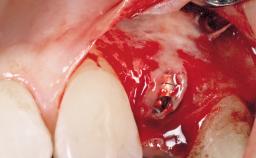

Early Placement of an Implant in a Maxillary Right Central Incisor Site

This 41-year-old female patient was referred to the clinic for the replacement of the right central incisor, since the tooth had developed a root fracture in the long axis that made extraction necessary. The healthy, non-smoking patient was first seen with the tooth still in place. A detailed Esthetic Risk Assessment was performed.The patient was worried about her dental esthetics and had high expectations for a successful treatment outcome from an esthetic point of view. The patient had a medium lip line that displayed parts of the gingiva in the anterior maxilla upon smile.

Bone Volume Deficient horizontally, allowing simultaneous augumentation